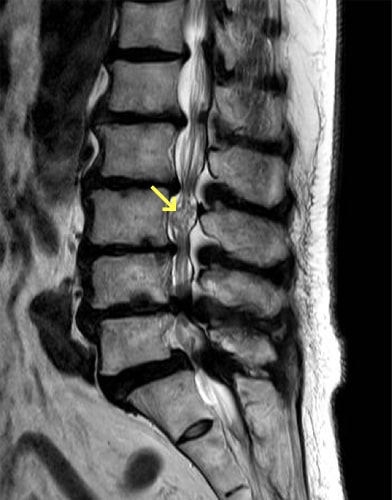

脊椎分離症とすべり症

疲労骨折などにより椎骨が椎弓の関節突起間部で分離したものを脊椎分離症といい、さらに分離した椎体が前方へ転位したものを脊椎すべり症といいます。日本人男性の約8%にみられ、成長期のスポーツ選手の腰痛の原因の30~40%を占めます。症状は腰部から臀部、大腿後面の痛み、背部・分離部の圧痛・叩打痛、神経性間欠跛行などです。治療法としては保存療法と手術療法がありますが、慢性期で痛みが強くない限りは手術は行わず保存療法となります。保存療法は、コルセットや体幹ギプスなどによる固定や運動の制限を急性期には行い、慢性期では薬物療法・分離部のブロック注射などの対症療法に加え、脊椎の負担のかからない動作や姿勢の指導、体幹筋のトレーニングを始めとした理学療法を行います。